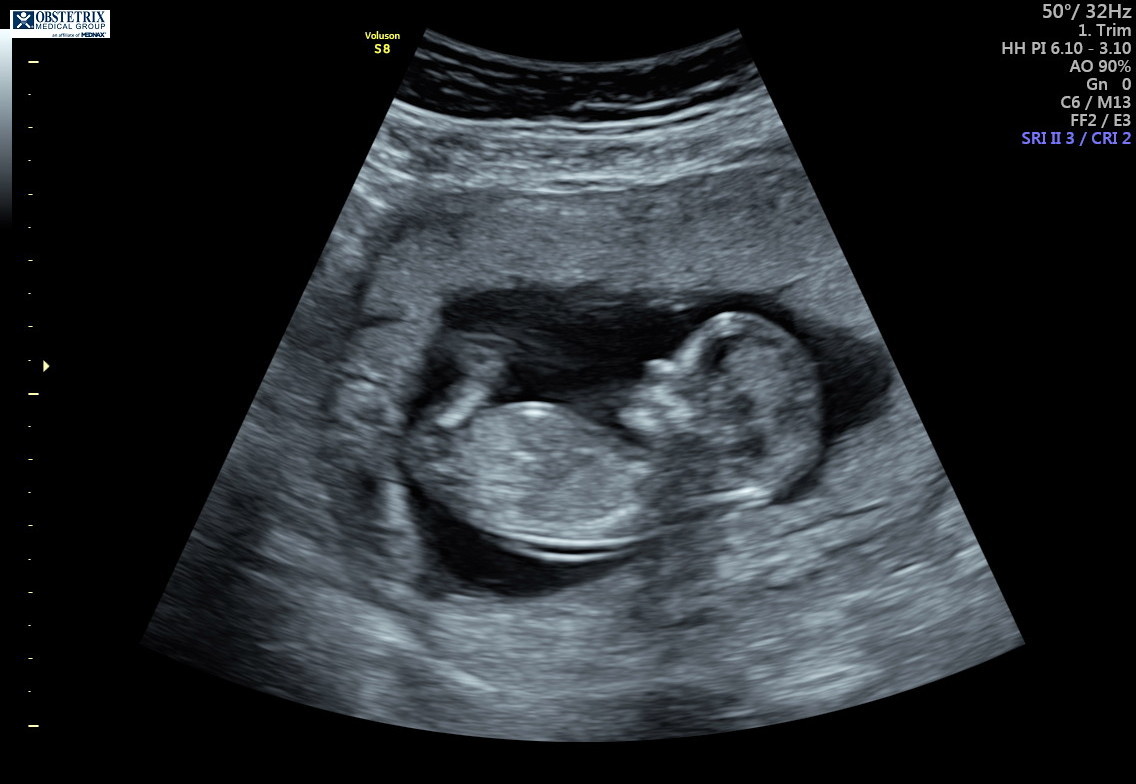

Everyone on my pregnancy app thinks this is a boy due to the skull. Any possibility of girl still?? After 4 boys, I am praying! The cord was between the legs the whole time so we didn't get a nub look or picture :( 12 weeks and 5 days